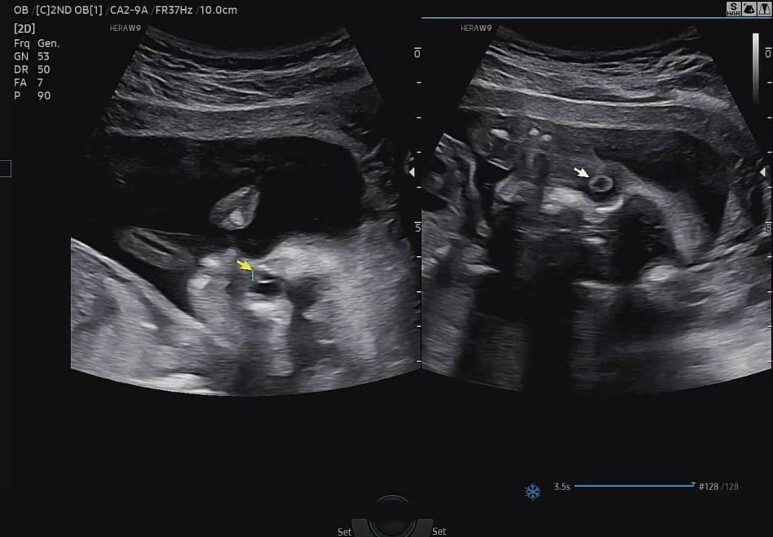

양쪽 수정체 확인.

오른쪽은 좀 무섭군..ㅎㅎ